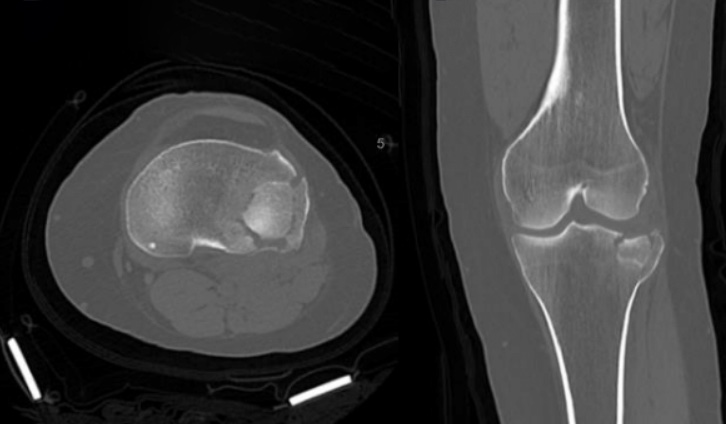

Answer: tibial plateau fracture

- obtain CT if no acute findings on xray and pt unable to bear weight. This patients CT is shown below.